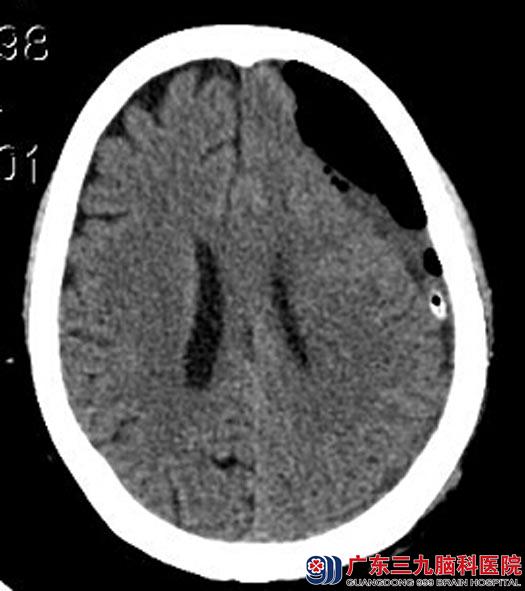

完善相关检查后,行左侧慢性硬膜下血肿引流术,术中见陈旧性血流出,伴有血凝块,术腔反复冲洗,直至没有血性液体流出。术后郭奶奶右侧肢体乏力症状明显好转,活动自如,顺利康复出院。

手术后